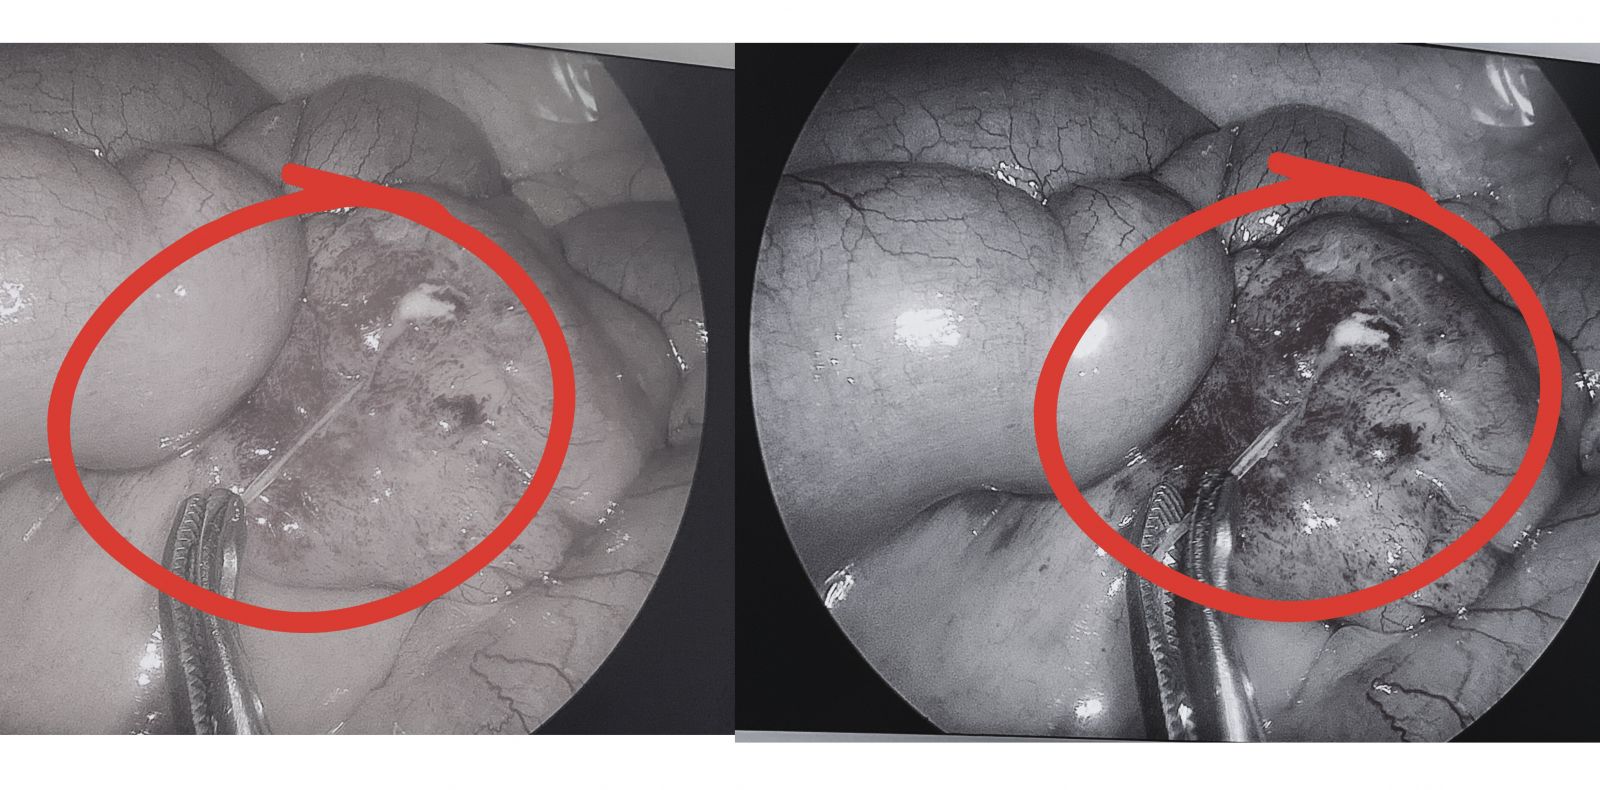

Hình ảnh trong phẫu thuật gắp mảnh xương cá đối nằm trong đoạn cuối ruột non của người bệnh Xuyến.

Ca phẫu thuật nội soi cấp cứu được tiến hành ngay, các bác sĩ đã lấy ra mảnh xương cá nhọn đâm xuyên thành ruột, xử lý ổ viêm nhiễm và khâu lỗ thủng ruột non.